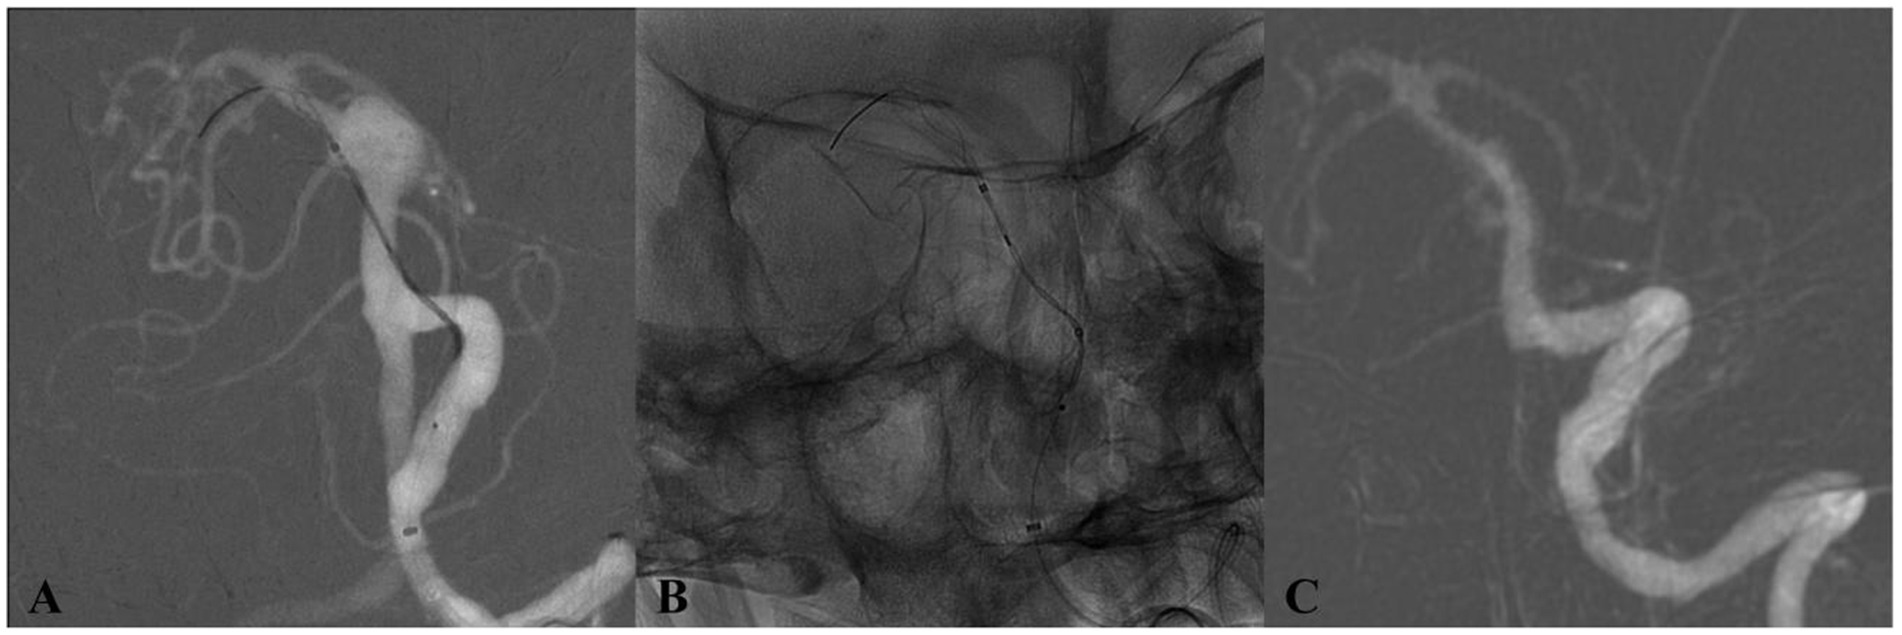

Three grayscale medical imaging panels labeled A, B, and C. Panel A shows a contrast-enhanced image of intricate vascular structures. Panel B displays an X-ray with visible catheter placement. Panel C illustrates a detailed view of a curved arterial section.

Figure 4. DSA of a patient from the 65–69 age group (Case 4) with an incidentally discovered basilar trunk aneurysm. (A) Preoperative angiography depicts an 11 × 10 mm aneurysm at the basilar trunk. (B) Immediate postdeployment DSA following placement of a single Tubridge flow diverter. (C) 17-month follow-up DSA demonstrates full aneurysm occlusion.